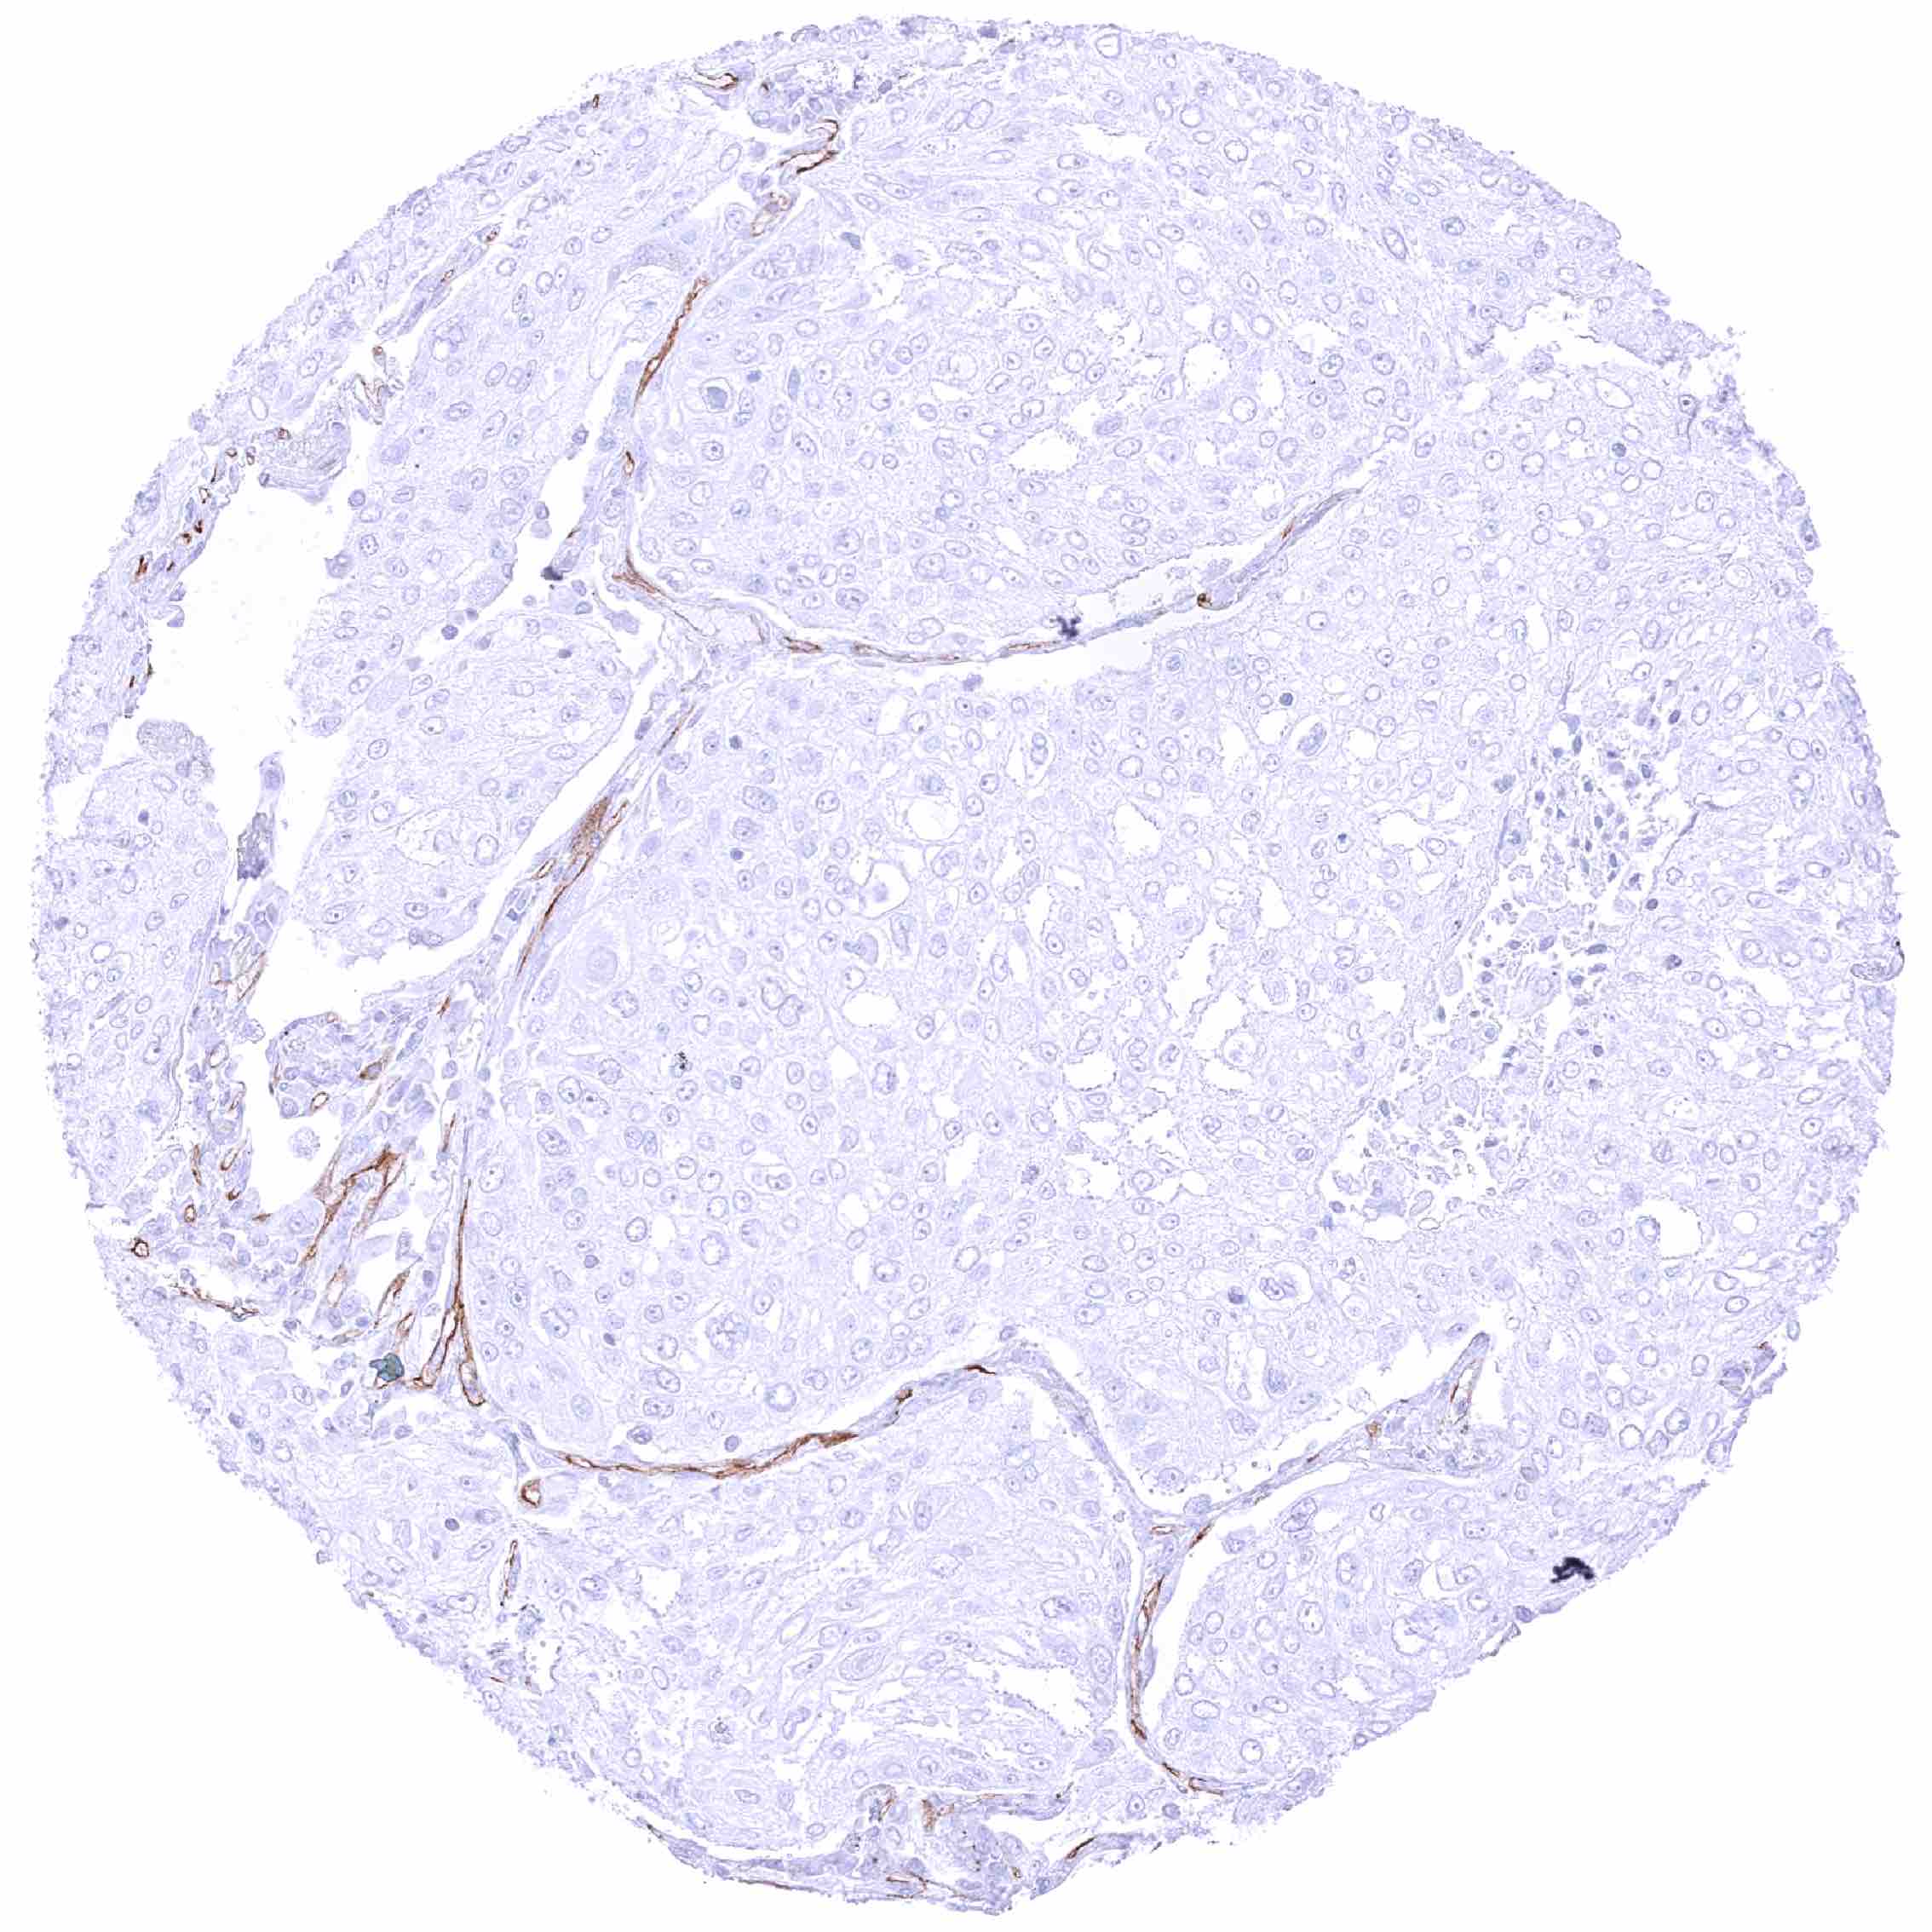

Urinary bladder – PODXL negative muscle-invasive urothelial carcinoma. Distinct PODXL positivity of endothelial cells of few vessels.